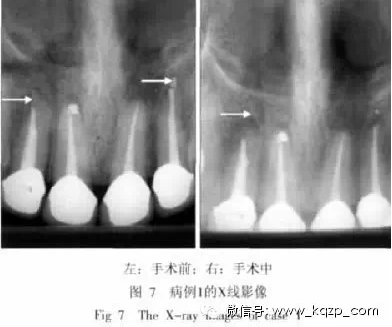

4、型病例

典型病例1,患者為女性,22歲。6個月前,因美觀需要在外院作上頜前牙根管治療后安裝烤瓷冠,2周后,2個上頜側(cè)切牙出現(xiàn)咬合不適,拆除根管充填物后重作根管治療,癥狀仍未好轉(zhuǎn),于上海交通大學(xué)醫(yī)學(xué)院附屬第九人民醫(yī)院口腔特需科就診。拍攝X線牙片,見22超充,12根尖處似有斷針(圖7左箭頭示)。因雙側(cè)側(cè)切牙已作烤瓷冠,故考慮作根尖刮除術(shù)。術(shù)中取出12根尖處斷針,刮除22超充物;術(shù)中拍攝牙片,再次仔細(xì)觀察發(fā)現(xiàn),12根尖偏近中處還有一密度較高的線形物(圖7右箭頭示)。手術(shù)取出,發(fā)現(xiàn)為長約4 mm的牙膠尖。術(shù)后1周復(fù)診,患者訴癥狀消除。

該病例曾去除充填物重作根管治療,考慮可能為第一次根管治療時牙膠尖超充(未見牙片),去除充填物時把超充的牙膠尖推出根尖后,又出現(xiàn)斷針。該病例較少見,但提示臨床醫(yī)生一定要仔細(xì)觀察牙片,防止遺漏異物。